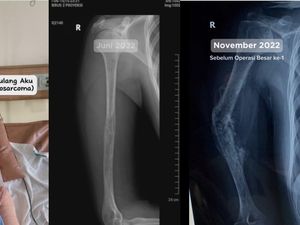

Awal Mula Wanita Bandung Idap Kanker Tulang, Diduga gegara Diurut dan Riwayat Jatuh

Berawal dari pegal biasa, seorang wanita di Bandung didiagnosis kanker tulang osteosarkoma. Dokter yang memeriksanya menduga kanker tersebut disebabkan hal ini.